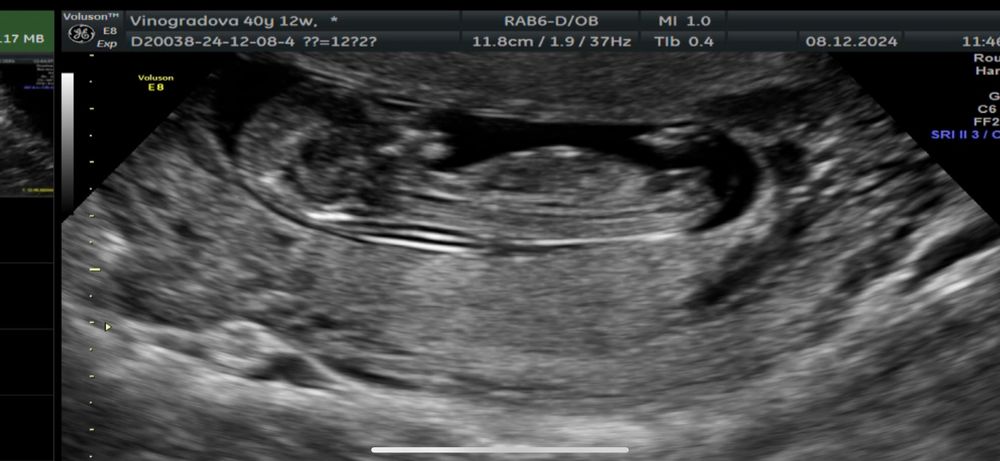

Узи 12 недель ❤️ Погадаем кто?

Врач сказал что может предположить пол лишь на 60%… Но так же интересно погадать 😅

Мне по половому бугорку видится девчуля… а вам?))

Я вообще подумала бы пацан по первому снимку но у нас 3 точно такой же и нам сказали девочка на 90%

Яна, врач в начале узи тоде сказал что похоже на мальчика 😂 ( как раз там где 1 фото и стрелочка))) а в конце узи сказал, нет, я меняю мнение - это скорее всего девочка. Но я думала он мог изменить мнение тк в процессе узи узнал что у нас уже 2 сына 😂 Решил мне надежду оставить 😂